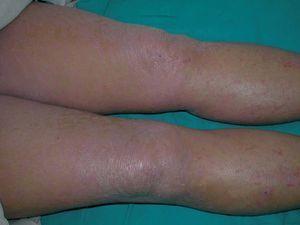

Existían 4 tipos de lesiones cutáneas: en antebrazos, muslos y piernas las lesiones consistían en pápulas planas poligonales confluentes con brillo blanquecino (fig. 1). En manos y pies, tanto en el área dorsal como palmoplantar, existía una hiperqueratosis con descamación foliácea, con edema severo subyacente (fig. 2). En el resto de las extremidades y en el tronco existía un eritema descamativo generalizado con tinte violáceo (fig. 3). Por último, se encontraron ampollas tensas en rodillas y dorso de pies, algunas de contenido hemorrágico (fig. 2). El signo de Nikolsky era negativo.

Fig. 1.—Lesiones en miembros inferiores: pápulas planas violáceas confluentes con brillo blanquecino.